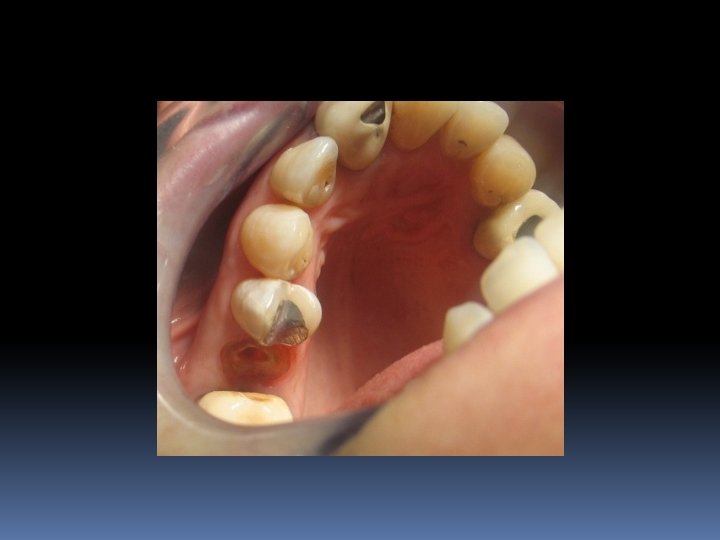

• Endodontik tedavi gören dişlerde, kök kanal girişinin açılması ya da çürük, kırık gibi nedenlerle aşırı madde kaybı bulunabilir. • Bu dişler kırılmaya karşı koruma altına alınmalıdır. • Bu amaçla, kök kısmında hazırlanan uygun bir kaviteye, yine uygun çap ve boyda bir post konularak tutuculuk; kron kısmına yapılan restorasyon yani kor ile de yapıya kron içi desteklik sağlanır.

“Post-Kor” restorasyonlarının endikasyonları 1. Aşırı derecedeki madde kayıplarında, 2. Travma sonucu oluşan kron kırıklarında 3. Erozyon gibi aşınmalar sonucu derin madde kayıplarında 4. Diş akslarının düzeltilmesinde, 5. Teleskop kronların kullanımında, dişlerin “post-kor” yada yalnız “kor” alt yapısı ile restore edilmesi gerektiğinde.

Sadece aşırı harabiyet gösteren dişler post kor ile restore edilmeli, ufak harabiyetlerde post kullanılmamalıdır.